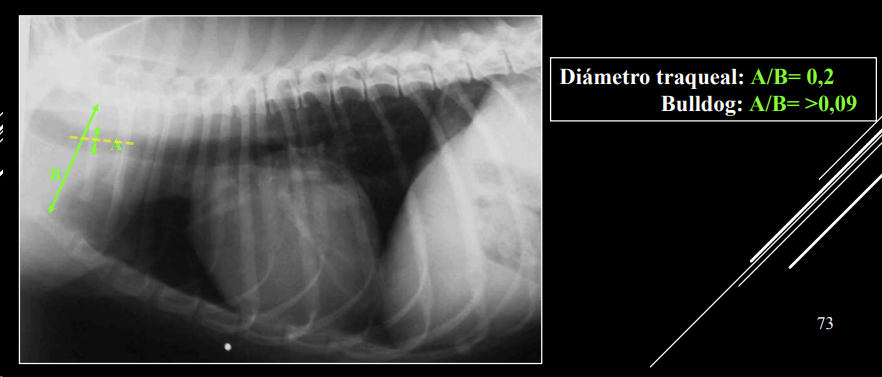

- Alteraciones del diámetro:

- Índice A/B = 0,2 (Bulldog ≥ 0,09).

- Hipoplasia traqueal: disminución generalizada del diámetro (congénita, braquicéfalos).

- Colapso traqueal: deformación de cartílagos, “tos de ganso”, inspiratorio, espiratorio o mixto. en razas toy. Degenerativa y progresiva